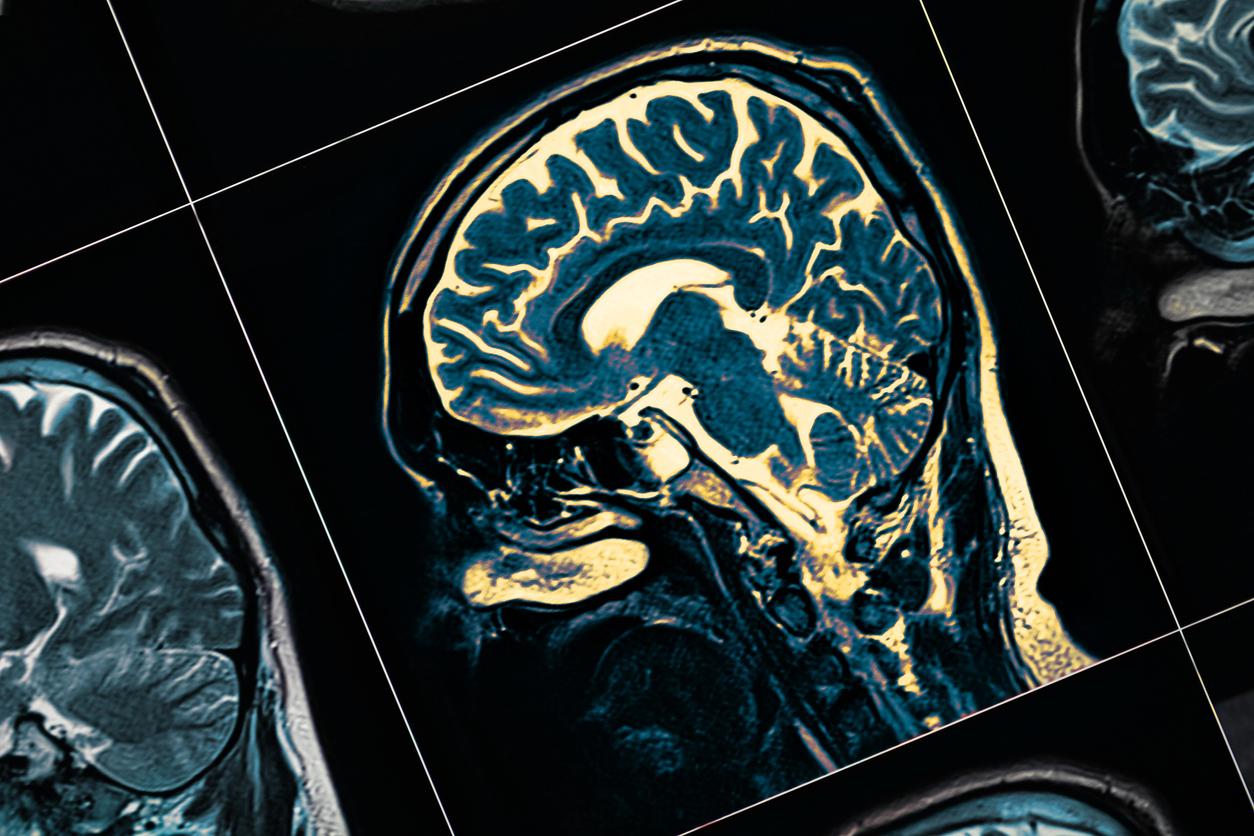

1,2 million de personnes sont atteintes de la maladie d’Alzheimer en France, selon l’Assurance maladie. Cette pathologie neurodégénérative est la plus fréquente dans l’Hexagone. Pour l’instant, il n’existe pas de traitement curatif : les seuls proposés visent à ralentir son évolution. Mais peut-on prévenir la maladie en amont ?